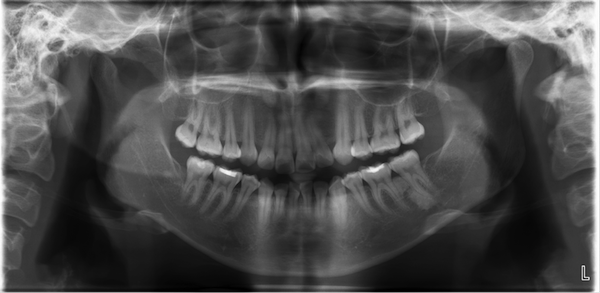

Osteosarcoma In A 30 Year Old Man Panoramic Radiograph Shows A Download Scientific Diagram From researchgate.net

DEFINISIPesawat dental x-ray panoramic adalah suatu peralatan di bidang radiologi yang digunakan untuk menangkap seluruh bagian mulut dalam suatu gambar termasuk gigi ata dan rahang bawah struktur dan jaringan sekitarnya dengan menggunakan sinar-x. Rontgen gigi juga disebut dengan radiografi gigi atau sinar X gigi. Rontgen gigi atau dental X-ray adalah prosedur medis untuk mengambil gambar bagian dalam mulut menggunakan cairan radiasi. Indirect conversion is so named because this technique still uses a scintillator to convert x. 11-32 A-C the PA does not show the transported canal and extent of short fill which is more evident in the CBCT.